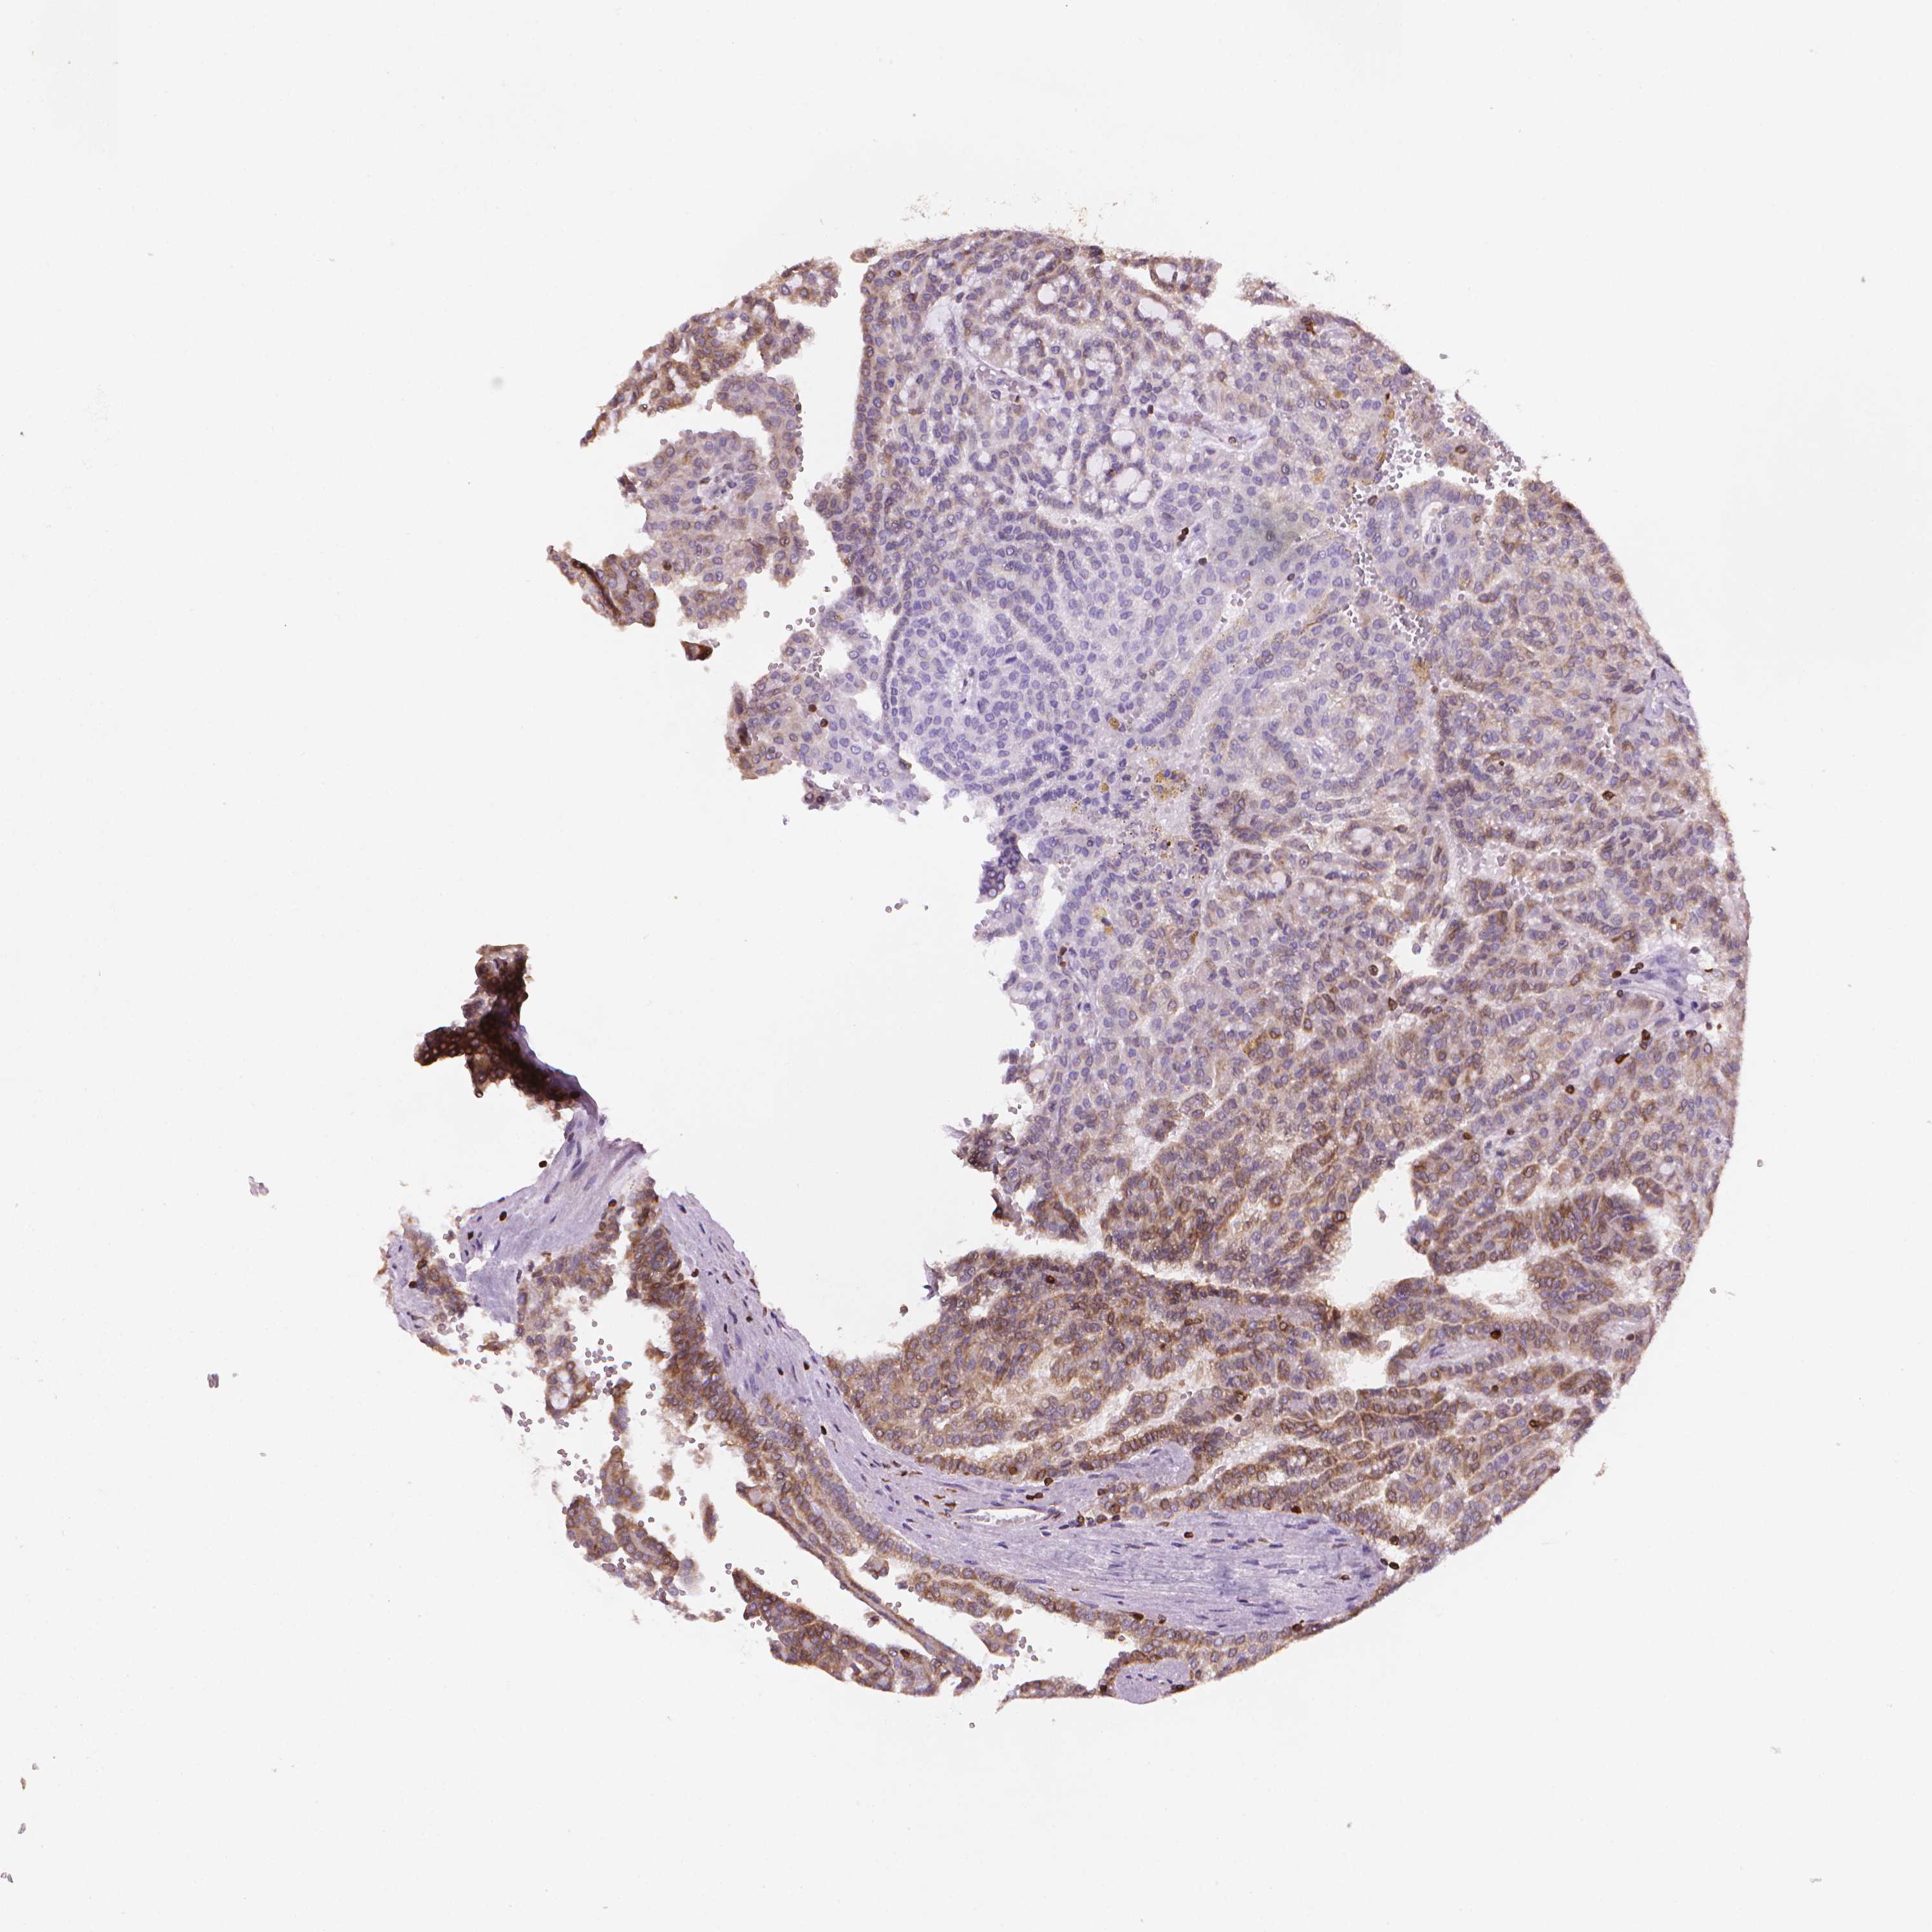

Renal cancer

Kidney chromophobe

KIDNEY CHROMOPHOBE (TCGA) - Interactive survival scatter ploti

The Survival Scatter plot shows the clinical status (i.e. dead or alive) for all individuals in the patient cohort, based on the same data that underlies the corresponding Kaplan-Meier plots. Patients that are alive at last time for follow-up are shown in blue and patients who have died during the study are shown in red.

The x-axis shows the expression levels (FPKM) of the investigated gene in the tumor tissue at the time of diagnosis. The y-axis shows the follow-up time after diagnosis (years). Both axes are complimented with kernel density curves demonstrating the data density over the axes. The top density plot shows the expression levels (FPKM) distribution among dead (red) and alive patients (blue). The right density plot shows the data density of the survived years of dead patients with high and low expression levels respectively, stratified using the cutoff indicated by the vertical dashed line through the Survival Scatter plot. This cutoff is automatically defined based on the FPKM cutoff that minimizes the p-score. The cutoff can be changed by dragging the vertical line or by entering a cutoff value in the square labeled "Current cut-off".

Under the Survival Scatter plot the p-score landscape (black curve; left axis) is shown together with dead median separation (red curve; right axis). Dead median separation is the difference in median mRNA expression between patients who have died with high and low expression, respectively. It is calculated as follows: median FPKM expression of dead patients with high expression - median FPKM expression of dead patients with low expression. This is intended to aid the user in visually exploring custom cutoffs and the associated p-scores and dead median separation.

Individual patient data is displayed and can be filtered by clicking on one or more of the category buttons on the top of the page. Categories describing expression level and patient information include: high, low, alive, dead, female, male and tumor stages. The scale of the x-axis can be toggled between linear and log-scale by clicking on the "x log" button. Mouse-over function shows TCGA ID, patient information and mRNA expression (FPKM) for each patient.

& Survival analysisi

Kaplan-Meier plots summarize results from analysis of correlation between mRNA expression level and patient survival. Patients were divided based on level of expression into one of the two groups "low" (under cut off) or "high" (over cut off). X-axis shows time for survival (years) and y-axis shows the probability of survival, where 1.0 corresponds to 100 percent.

BCL2 is not prognostic in Kidney Chromophobe (TCGA)